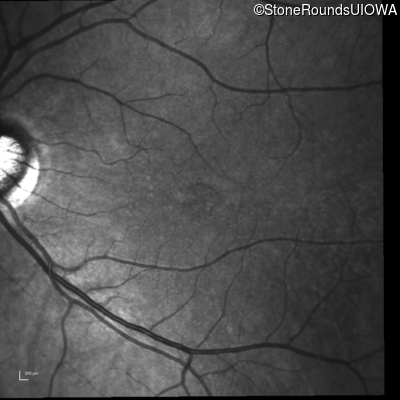

Infrared Fundus Photograph - Right - 20/20 -1

Exemplar